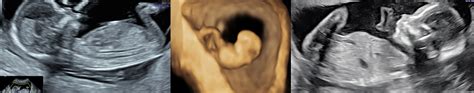

Poloha placenty býva dôsledne monitorovaná najmä pri 18. až 21. týždňovom ultrazvukovom vyšetrení. Neskôr počas tehotenstva (zvyčajne okolo 32. týždňa) ženy absolvujú ďalší ultrazvuk, aby sa znova skontrolovala jej poloha. U 9 z 10 žien je placenta v tomto bode už v hornej časti maternice. Ak je placenta stále nízko v lone, zvyšuje sa šanca, že počas tehotenstva alebo pôrodu dôjde ku krvácaniu. Býva spravidla veľmi silné a ohrozuje matku aj dieťa. Spravidla, ak je placenta blízko alebo pokrýva krčok maternice, dieťa nemôže prísť na svet cez vagínu, preto sa odporúča cisársky rez.